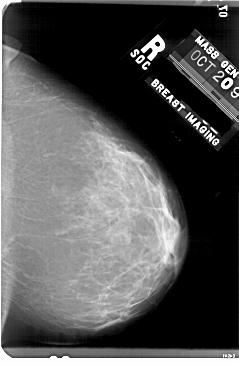

A_1758_1.RIGHT_MLO

RIGHT_MLO LINES 5206 PIXELS_PER_LINE 3376 BITS_PER_PIXEL 12 RESOLUTION 43.5 NON_OVERLAY